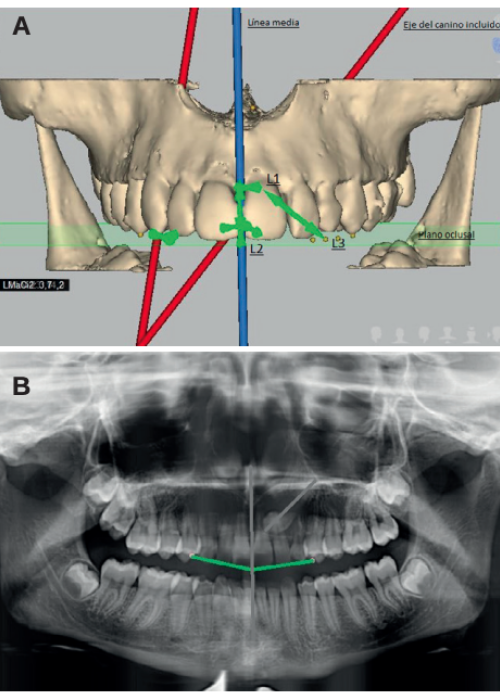

Radiographic diagnosis of impacted maxillary canines: Comparison between two and three dimensions